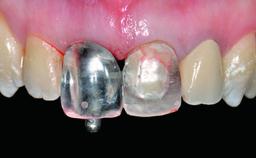

Replacement of a Perforated Upper Left Central Incisor: Early Placement of an RC Bone Level Implant

A 28-year-old patient presented at her general dentist’s office and complained about the appearance of her tooth 21. The patient had a history of trauma to this tooth. Endodontic treatment had been performed in the past and a crown placed on the tooth. A procedure to replace the old crown was performed by her dentist; however, a perforation on the middle third of the root occurred, and extraction of tooth 21 was suggested. Upon clinical and radiographic examination of the patient, who had been referred to us, replacement of tooth 21 by a dental implant appeared to be indicated.